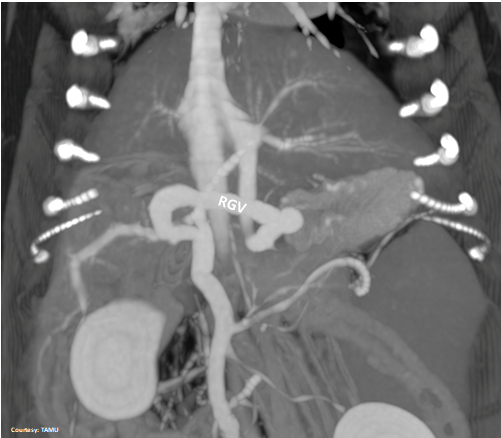

Does the RIGHT GASTRIC VEIN (RGV) contribute blood to the shunt?